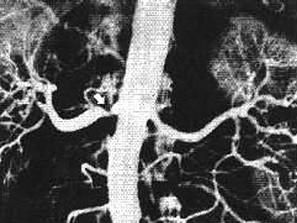

问题 女,28岁,头痛、头晕、心悸、视力减退2年,多次在当地医院检查,诊断为高血压症,用一般降压药无效,无高血压家族史。体查:血压190/110mmHg,脉搏90次/分,体型中等,心、肺、肝未见异常,腰背部闻及收缩期吹风样杂音。 肾血管性高血压诊断确立后,如需了解狭窄的部位、范围、程度以及有无狭窄后扩张现象,应作以下哪项检查 ( )

选项 A、IVU B、肾图 C、肾动脉造影 D、CT E、B超

答案 C